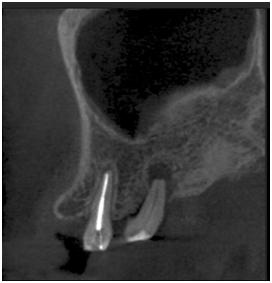

这位姐姐也说做了根管的

但是根管里面就细细的两根牙胶尖,根本没有填满